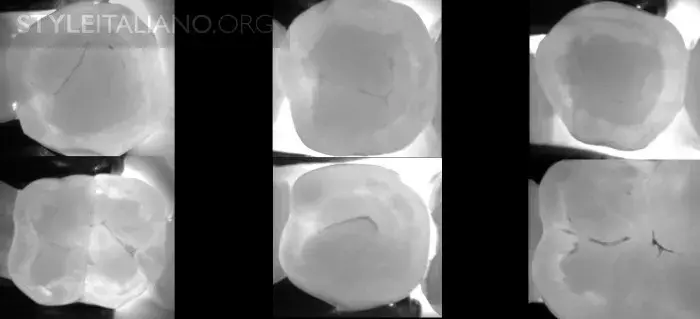

Рис. 15 — Предоперационный вид/ Лазерное просвечивание/ Рентген.

Рис. 16 – Просвечивание зубов показывает полости в истинном размере, а на рентгене они уменьшены.

Рис. 18 — До, во время и после лечения.